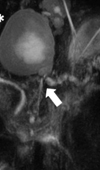

Transpapillary Drainage of Persistent Pseudocyst Causing Dysphagia

A 47-year-old female with history of chronic alcohol-related pancreatitis presented with dysphagia and mild weight loss. Esophagram demonstrated a str... Read more

10.36959/879/379